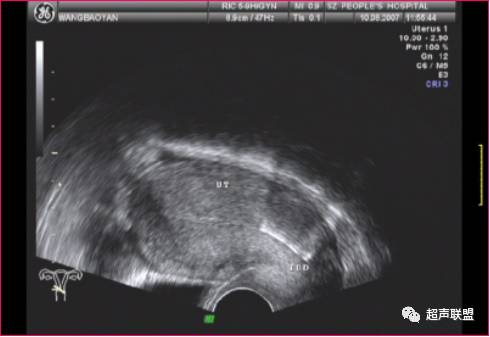

节育器外游

超声表现为子宫腔内无节育器显示,节育器可穿透宫壁落入腹腔,包裹于肠管中,从而形成纤维粘连或机化,在腹腔内、阔韧带、附件区或直肠窝区有强回声节育器图像。节育器外游至盆腔,因肠道气体干扰不易寻找,应多角度仔细观察,节育器外游至肠间与肠道气体相混不易分辨,超声仪无能为力,须借助X线检查。偶尔IUD可穿入膀胱,此时可见带有彗星尾征的强回声带穿过膀胱壁而进人膀胱腔。鉴别诊断:节育器外游至膀胱须与膀胱结石相鉴别,结石随患者体位不同而改变,位置变化较大,节育器多因炎性粘连而固定不动。

节育环(IUD)位于宫颈(CX)左侧的盆腔内.

(经阴道超声)